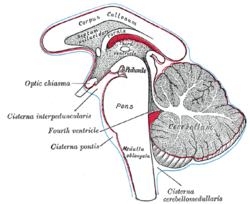

Tela chorioidea of the third ventricle, and the choroid plexus of the left lateral ventricle, exposed from above. Diagram showing the positions of the three principal subarachnoid cisternæ.

Diagram showing the positions of the three principal subarachnoid cisternæ.- Fornix